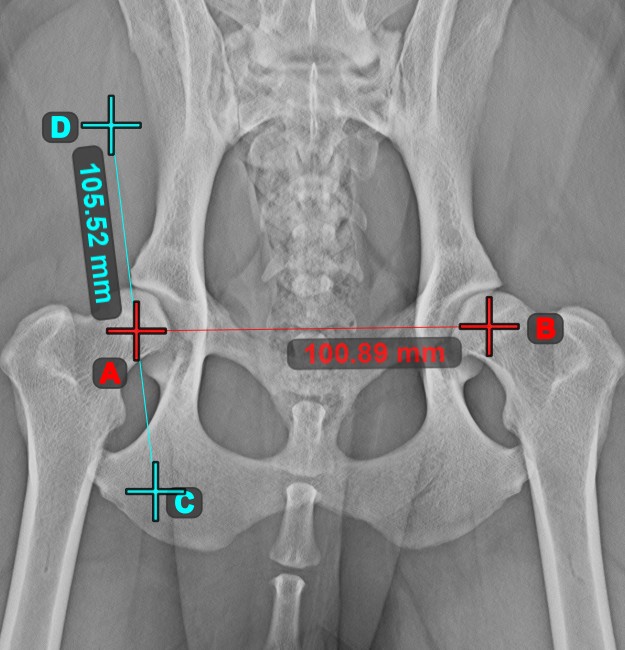

Line Measurement¶

Select the Line Measurement

tool and assign it to one of the available mouse buttons. Place the start and end points on the scene or select them from already existing points on the image. The distance between the two points will be automatically

calculated by using the default calibration data, or the recalibrated data by the length calibration measurement.

Measurement Point¶

Measurement Point

tool. Each point is assigned with a letter for better identification.Select/Move Item

tool. Select the point by using the assigned mouse button of the tool, and then move it freely anywhere on the image.